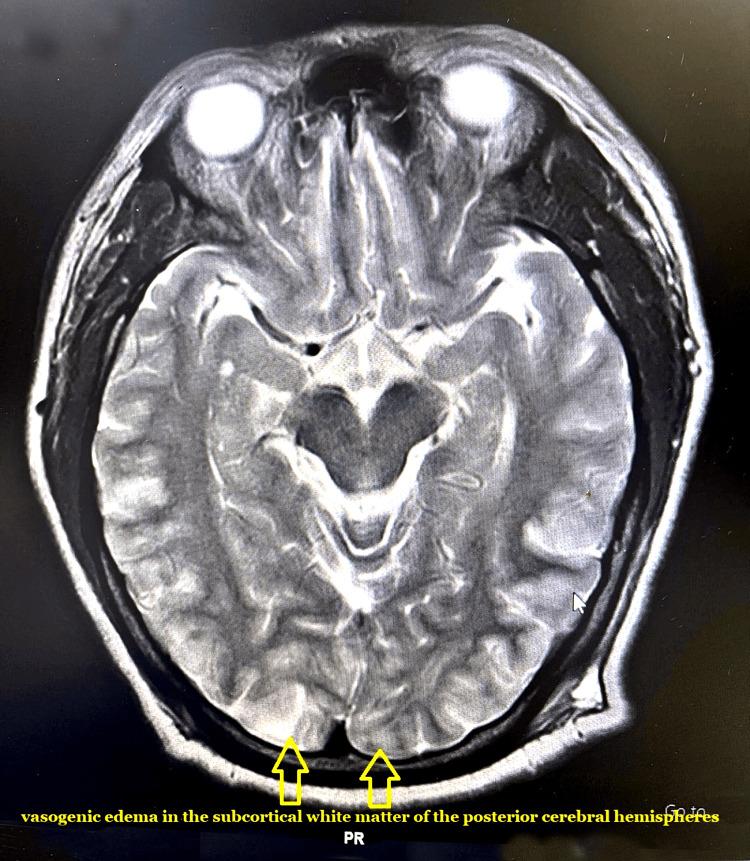

Recently, there has been a rise in reports of posterior reversible encephalopathy syndrome (PRES), which is an uncommon neurologic illness. The precise cause of PRES syndrome is yet unknown, but there are certain illnesses that have been associated with it. Furthermore, because of advances in imaging methods and growing awareness, the connection between PRES and pre-eclampsia/eclampsia is becoming increasingly recognised. Pre-eclampsia/eclampsia by itself poses distinct perioperative difficulties; in addition, PRES makes anesthesia administration more difficult. Regretfully, there is a lack of knowledge regarding the anesthetic treatment provided to the extremely sick and medically complex patients, and it is uncertain whether the chosen anesthetic might exacerbate neurologic problems. Here, we discuss the implications for the anesthetic management of PRES presentations.

最近,关于后部可逆性脑病综合征(PRES)的报告有所增加,这是一种罕见的神经系统疾病。PRES综合征的确切病因尚不清楚,但有某些疾病与之相关。此外,由于成像方法的进步和认识的提高,PRES与子痫前期/子痫之间的关联越来越受到认可。子痫前期/子痫本身会带来独特的围手术期困难;此外,PRES会使麻醉管理更加困难。遗憾的是,对于为病情极其严重且医疗情况复杂的患者提供的麻醉治疗缺乏了解,并且不确定所选择的麻醉是否会加重神经问题。在此,我们讨论PRES表现对麻醉管理的影响。